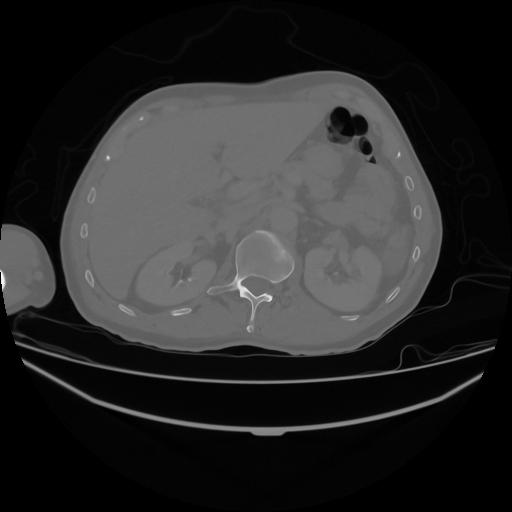

5 CUERPO,CE,Vol,1.0,CUERPO,,